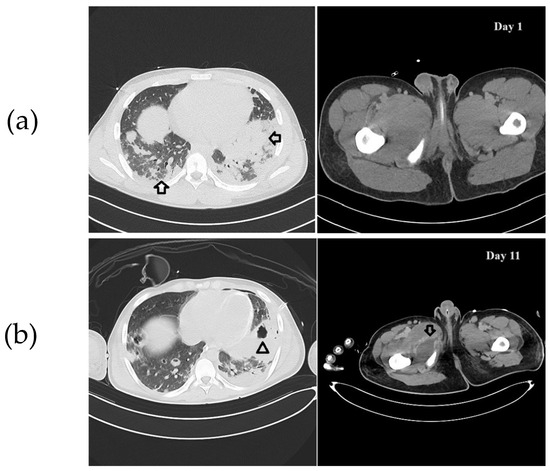

2. Case Description